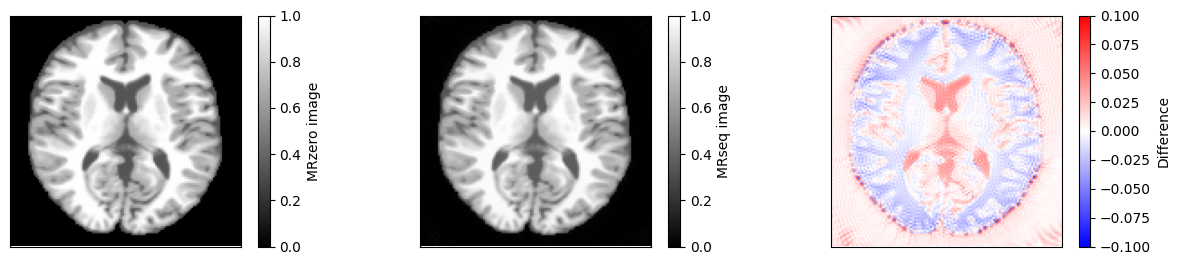

fig, ax = plt.subplots(1, 3, figsize=(15, 3))

for cax in ax:

cax.set_xticks([])

cax.set_yticks([])

im = ax[0].imshow(idat_model, vmin=0, vmax=1, cmap='gray')

fig.colorbar(im, ax=ax[0], label='MRzero image')

im = ax[1].imshow(idat, vmin=0, vmax=1, cmap='gray')

fig.colorbar(im, ax=ax[1], label='MRseq image')

im = ax[2].imshow(idat - idat_model, cmap='bwr', vmin=-0.1, vmax=0.1)

fig.colorbar(im, ax=ax[2], label='Difference')

relative_error = np.sum(np.abs(idat - idat_model)) / np.sum(np.abs(idat_model))

print(f'Relative error {relative_error}')

assert relative_error < 0.03

Relative error 0.02431044342663307